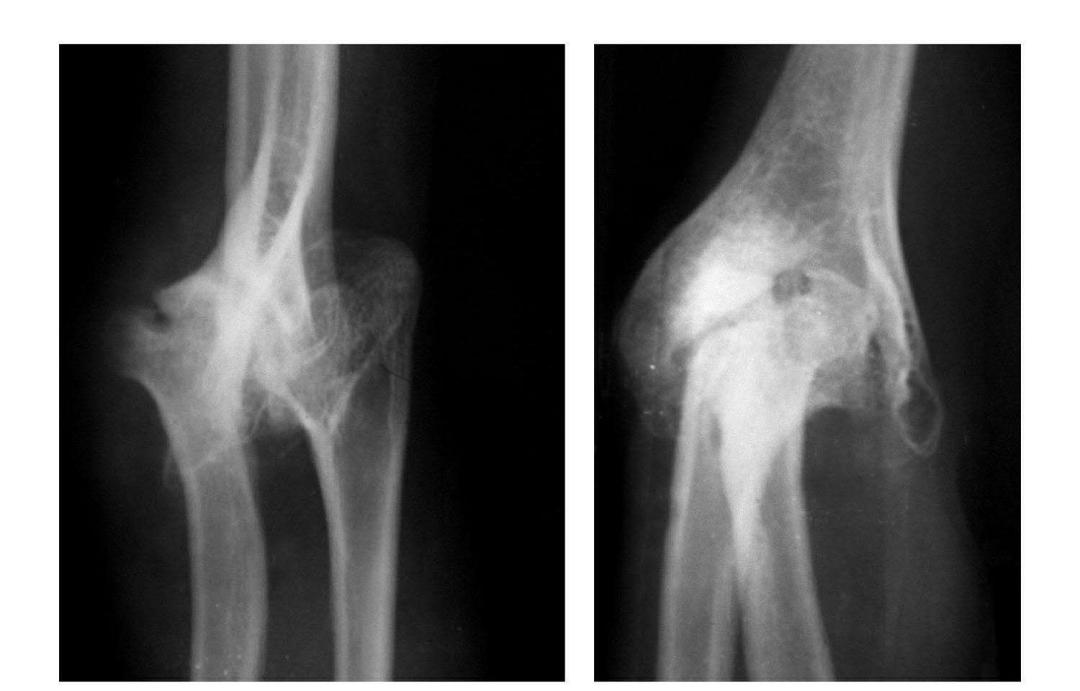

肱骨小头冠状面骨折

(一)完全骨折

本病亦称哈-斯(Hahn-Steinthal)型骨折

例1:肱骨小头基底部呈冠状面骨折,骨折块呈半球状向肘前上方移位。

例2:肱骨小头基底部冠状面骨折,骨折块呈半球状向肘前移位并肱骨内上髁无移位骨折。

例3:肱骨小头及滑车桡侧壁前半部呈整体性冠状面骨折,骨折块向前上移位并外髁骨折。